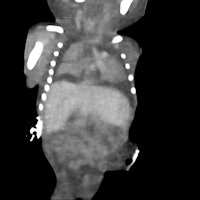

The fetuses were scanned as they arrived in the department of surgical pathology, wrapped in surgical drapes, and were not repositioned for the scan. To maximize contrast resolution, each fetus was imaged twice using a single-source spectral dual energy CT unit.

Firstly, a high-definition helical scan was completed permitting the maximum spatial resolution possible for multiplanar bone and 3D volume rendered skeletal imaging (3D skeleton). This was followed by a dual energy acquisition. Both high and low energy (kVp) datasets were acquired simultaneously for near perfect anatomical registration.

The dual energy image set was evaluated for the optimal image contrast and image noise. The optimal monochromatic energy level (keV) was concluded and a new image set was created for multiplanar evaluation of soft-tissue organs.

A conventional autopsy was performed on each fetus after CT scanning by an experienced pediatric/neonatal pathologist. The CT scans were analyzed by a perinatal radiologist (Constantine herself), together with a pediatric/neonatal pathologist (co-author Dr. Lynette Moore, an associate professor).

The clinical details (except gestational age) were withheld. The fetal biometry as well as findings relating to an external examination and internal organs were measured and recorded. The CT findings were then compared with the autopsy result, which was considered the gold standard.

Six fetuses were initially scanned. Three fetuses had been delivered after death in utero, and three were from pregnancies terminated due to fetal abnormalities. In all but one fetus, the crown-rump and crown-heel length measurements determined on CT were within 6% of the autopsy measurements. There was quite poor correlation between CT and autopsy measurements of the fetal foot length and head measurements, probably due to fetal positioning; the foot can be more easily "straightened" during a direct examination.